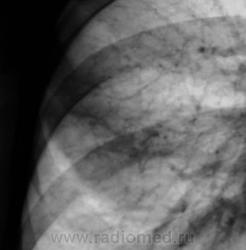

Контроль через 1 месяц после противовоспалительной терапии.